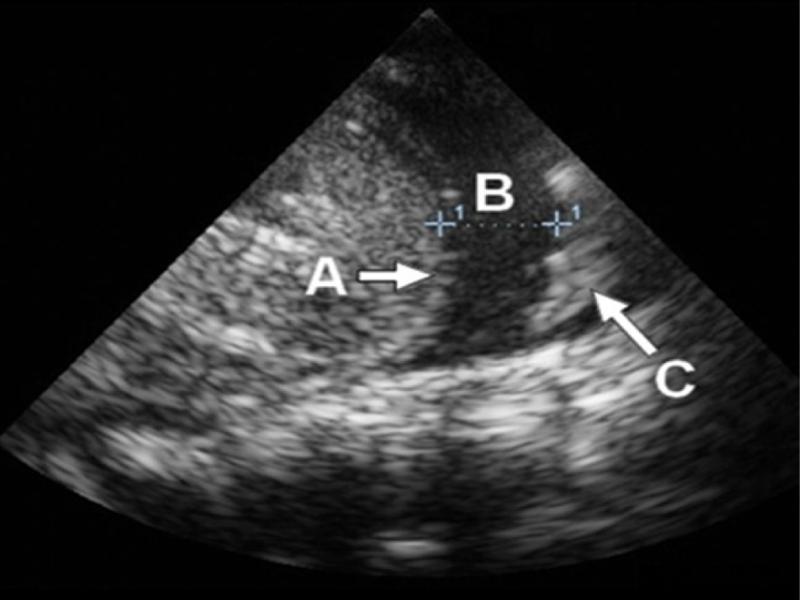

Fig. 1.

An ultrasound image of: A – diaphragm; B – pleural fluid; C – consolidated pulmonary parenchyma within the pulmonary tissue